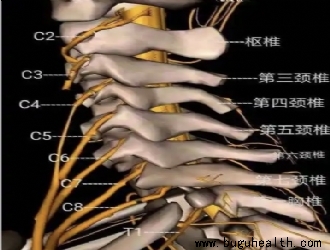

- “收下巴”这个动作,在康复领域通常被称为 “颈椎后缩”(Cervical Retraction),它是几乎所有颈椎康复训练的基石。 头前引姿势是颈椎病中常见的不当姿势――头部的重心在躯干的前侧。它导致颈部和头部的后伸肌组织(斜方肌上部、肩胛提肌、头半棘肌、头夹肌、颈夹肌、枕下肌群)持续收缩,前.....

- 布骨康复医学科普:颈椎曲度变直:成因、影响与应对之策 BuGuHealth ,2024-12-25

- 在现代生活中,颈椎曲度变直的现象却愈发普遍,给人们的健康带来诸多困扰。 颈椎曲度变直的形成与多种因素密切相关。长期不良的姿势堪称“罪魁祸首”之一。.....